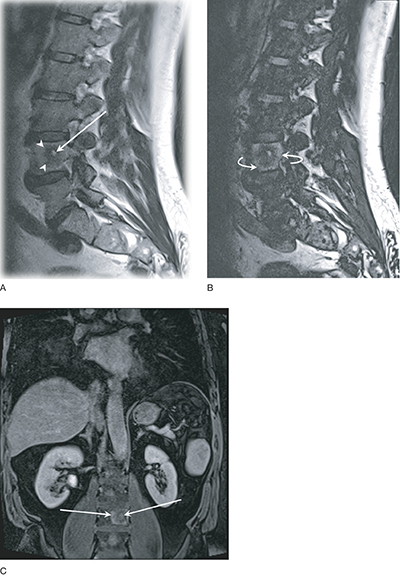

Epithelioid hemangioendothelioma (EHE) is a rare vascular tumor that can originate in various parenchymatous organs, soft tissue, and bone. Extrahepatic involvement is exceedingly rare. In this case, multifocal disease in the spleen and bone was present. Bone lesions showed a target appearance. Splenic lesions showed delayed enhancement of solid components with persistent rim enhancement. A bone biopsy with CAMTA1 staining confirmed the diagnosis. Teaching point: The presence of multifocal bone and splenic lesions can raise suspicion of EHE when other multifocal diseases are excluded.

上皮样血管内皮瘤(EHE)是一种罕见的血管肿瘤,可起源于各种实质性器官、软组织和骨骼。肝外受累极为罕见。在该病例中,脾脏和骨骼出现多灶性病变。骨病变呈靶状。脾脏病变显示实性成分延迟强化,边缘持续强化。经CAMTA1染色的骨活检确诊。教学要点在排除其他多灶性疾病的情况下,出现多灶性骨和脾病变可引起对 EHE 的怀疑。